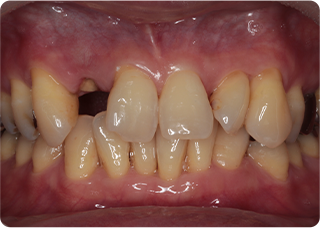

セラミッククラウン症例②

術前

仮歯

術後

| 主訴 | 前歯を綺麗にしたい、隙間が気になる |

|---|---|

| 治療期間/回数 | 4ヵ月、6回 |

| 価格(税込) | 792,000円(税込) |

| リスク・副作用 | セラミック破損の可能性 |

| ポイント | 仮歯で歯ぐきの状態を整え、自然な色、形となるようにオーダーメイドでセラミックを盛り、クラウンを作製した。 |